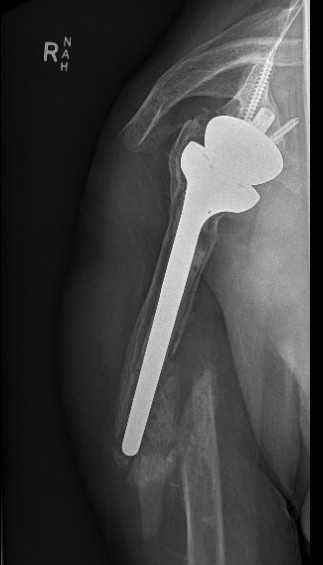

Dislocated Reverse TSRDislocated Reverse TSR Lateral

disdis